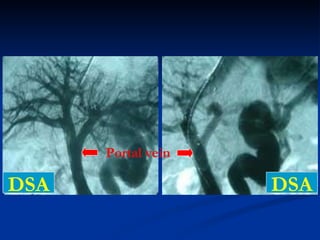

P ortal vein   stenosis

P ortal vein  thrombus

DSA DSA Portal vein